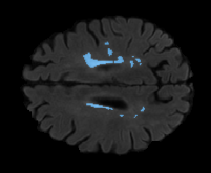

We evaluated our method in segmenting WMH from T1-w images using: a) Synthesized FLAIR images by treating the synthesis as a preprocessing step – we will refer to this method as offline synthesis; b) Synthesized FLAIR images using the proposed method, and c) without any synthesis – we will refer to this method as Unimodal. Baseline methods are illustrated in Figure 2

Unimodal

[Uncaptioned image] [Uncaptioned image] [Uncaptioned image]

Table 2: Segmentation results for all proposed methods, each column represent a different slide in the image, blue areas are regions which were correctly labeled, false positives are shown in green, and false negatives in yellow

In order to better understand the above results, we visually analyzed the output segmentation performed for each method. Table 2 shows the results for three different slices (one slice per column). As illustrated, the proposed method is able to produce less false positives. It is also important to note that, unimodal segmentation is the one that produces more false positives, showing the advantage of using synthetic data. Regarding the nature of false positives, it can be easy to see in the third column a large number of false positives are on the border of periventricular lesions for the Unimodal method in comparison to the proposed method. Also from the first and second column, it can be observed that Unimodal tend to produce more small regions of false positives near to cortical areas. Removing such false positives requires additional post-processing steps, therefore, it is of value avoid this kind of over-segmentation. It can also be noted that synthesis methods tend to produce the same kind of false negatives, this may be due to the blurring effects in synthesized images since the information available during testing is limited – which otherwise is available from a FLAIR sequence.